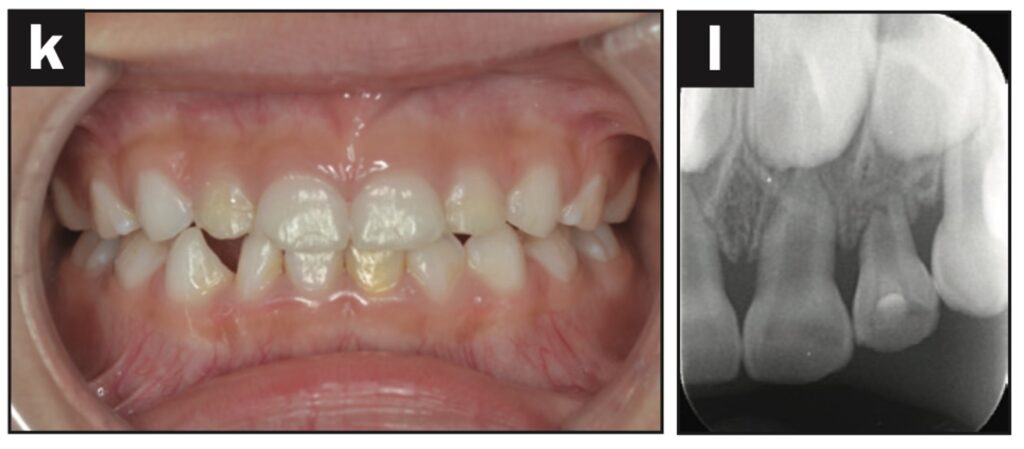

Bệnh nhân nữ 42 tuổi bị ngã khiến răng cửa giữa hàm trên bên trái bị lệch về phía vòm miệng. Đường gãy xương ổ răng ở phía khẩu cái được thấy trên CBCT.

Răng được nắn chỉnh và cố định bằng composite quang trùng hợp rồi lấy dấu. Hai tiếng sau, bệnh nhân quay lại và nhận khay duy trì. Bệnh nhân được hướng dẫn đeo khay duy trì cả ngày trừ khi đánh răng.

Các thử nghiệm tủy được thực hiện sau 7 và 28 ngày. Đánh giá độ lung lay răng, gõ và sờ, thử tủy EPT và chụp X quang được thực hiện sau 28 ngày.

Sau 28 ngày theo dõi, răng hơi lung lay và không đáp ứng với thử tủy EPT. Sau 2 tháng theo dõi, răng không bị đổi màu, không lung lay, âm tính với EPT và hơi nhạy cảm khi gõ. Không có tổn thương quanh chóp trên X quang và không có lỗ dò. Sau 3 tháng theo dõi, răng đã đáp ứng với EPT (9/10) và có cảm giác đau nhẹ khi gõ.

Sau 4 tháng theo dõi, răng đã phản ứng với EPT (9/10) và không còn nhạy cảm với gõ.